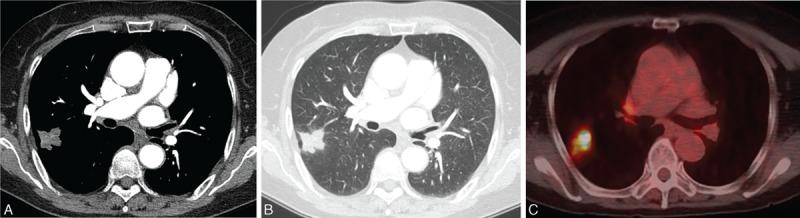

To describe the features and clinical implications of computed tomography (CT), positron emission tomography (PET), and percutaneous needle aspiration biopsy (PCNB) in pulmonary nontuberculous mycobacterial (NTM) disease manifesting as a solitary nodule, mass, or mass-like consolidation mimicking malignancy.Among a cohort of 388 patients with NTM pulmonary disease, 14 patients with clinically and radiologically suspected lung cancer were included in our study. Two chest radiologists evaluated CT features, including lesion type (nodule, mass, or mass-like consolidation), morphologic features (margin, degree of enhancement, calcification), and presence of accompanying findings suggestive of NTM pulmonary disease (bronchiectasis with clustered centrilobular nodules or upper-lobe cavitary lesions) by consensus. Diagnostic procedures for microbiologic diagnosis of NTM disease and clinical outcome were reviewed.Incidence of NTM pulmonary disease presenting as solitary nodule/mass (n = 8) or mass-like consolidation (n = 6) was 3.6% (14 of 388). Most lesions were detected incidentally during routine health check-up or evaluation of other disease (11 of 14, 79%). Lesions typically showed poor contrast-enhancement (9 of 12) and internal calcification (6 of 14). No lesions had CT features suggestive of NTM pulmonary disease. All 4 lesions for which PET/CT imaging was performed showed strong fluorodeoxyglucose uptake simulating malignant lesions (mean, 4.9; range, 3.6-7.8). PCNB revealed mycobacterial histology in 6 of 11 specimens and positive culture results were obtained for 7 of 7 specimens.NTM pulmonary disease may present as a solitary nodule, mass, or mass-like consolidation mimicking malignancy. CT features and PCNB are important to diagnose NTM disease mimicking lung cancer to avoid unnecessary surgery.

描述计算机断层扫描(CT)、正电子发射断层扫描(PET)和经皮针吸活检(PCNB)在表现为孤立性结节、肿块或类似肿块的实变影且疑似恶性肿瘤的肺非结核分枝杆菌(NTM)病中的特征及临床意义。在388例NTM肺病患者队列中,14例临床及影像学疑似肺癌的患者纳入本研究。两名胸部放射科医生通过共识评估CT特征,包括病变类型(结节、肿块或类似肿块的实变影)、形态学特征(边缘、强化程度、钙化)以及提示NTM肺病的伴随表现(伴有簇状小叶中心结节的支气管扩张或上叶空洞性病变)。回顾NTM病的微生物学诊断程序及临床结局。表现为孤立性结节/肿块(n = 8)或类似肿块的实变影(n = 6)的NTM肺病发生率为3.6%(388例中的14例)。大多数病变在常规健康检查或其他疾病评估期间偶然发现(14例中的11例,79%)。病变通常表现为强化不佳(12例中的9例)及内部钙化(14例中的6例)。无病变具有提示NTM肺病的CT特征。进行PET/CT成像的4例病变均显示强烈的氟脱氧葡萄糖摄取,类似恶性病变(平均值为4.9;范围为3.6 - 7.8)。11例标本中有6例PCNB显示分枝杆菌组织学,7例标本中有7例培养结果为阳性。NTM肺病可能表现为孤立性结节、肿块或类似肿块的实变影,疑似恶性肿瘤。CT特征及PCNB对于诊断疑似肺癌的NTM病以避免不必要的手术很重要。